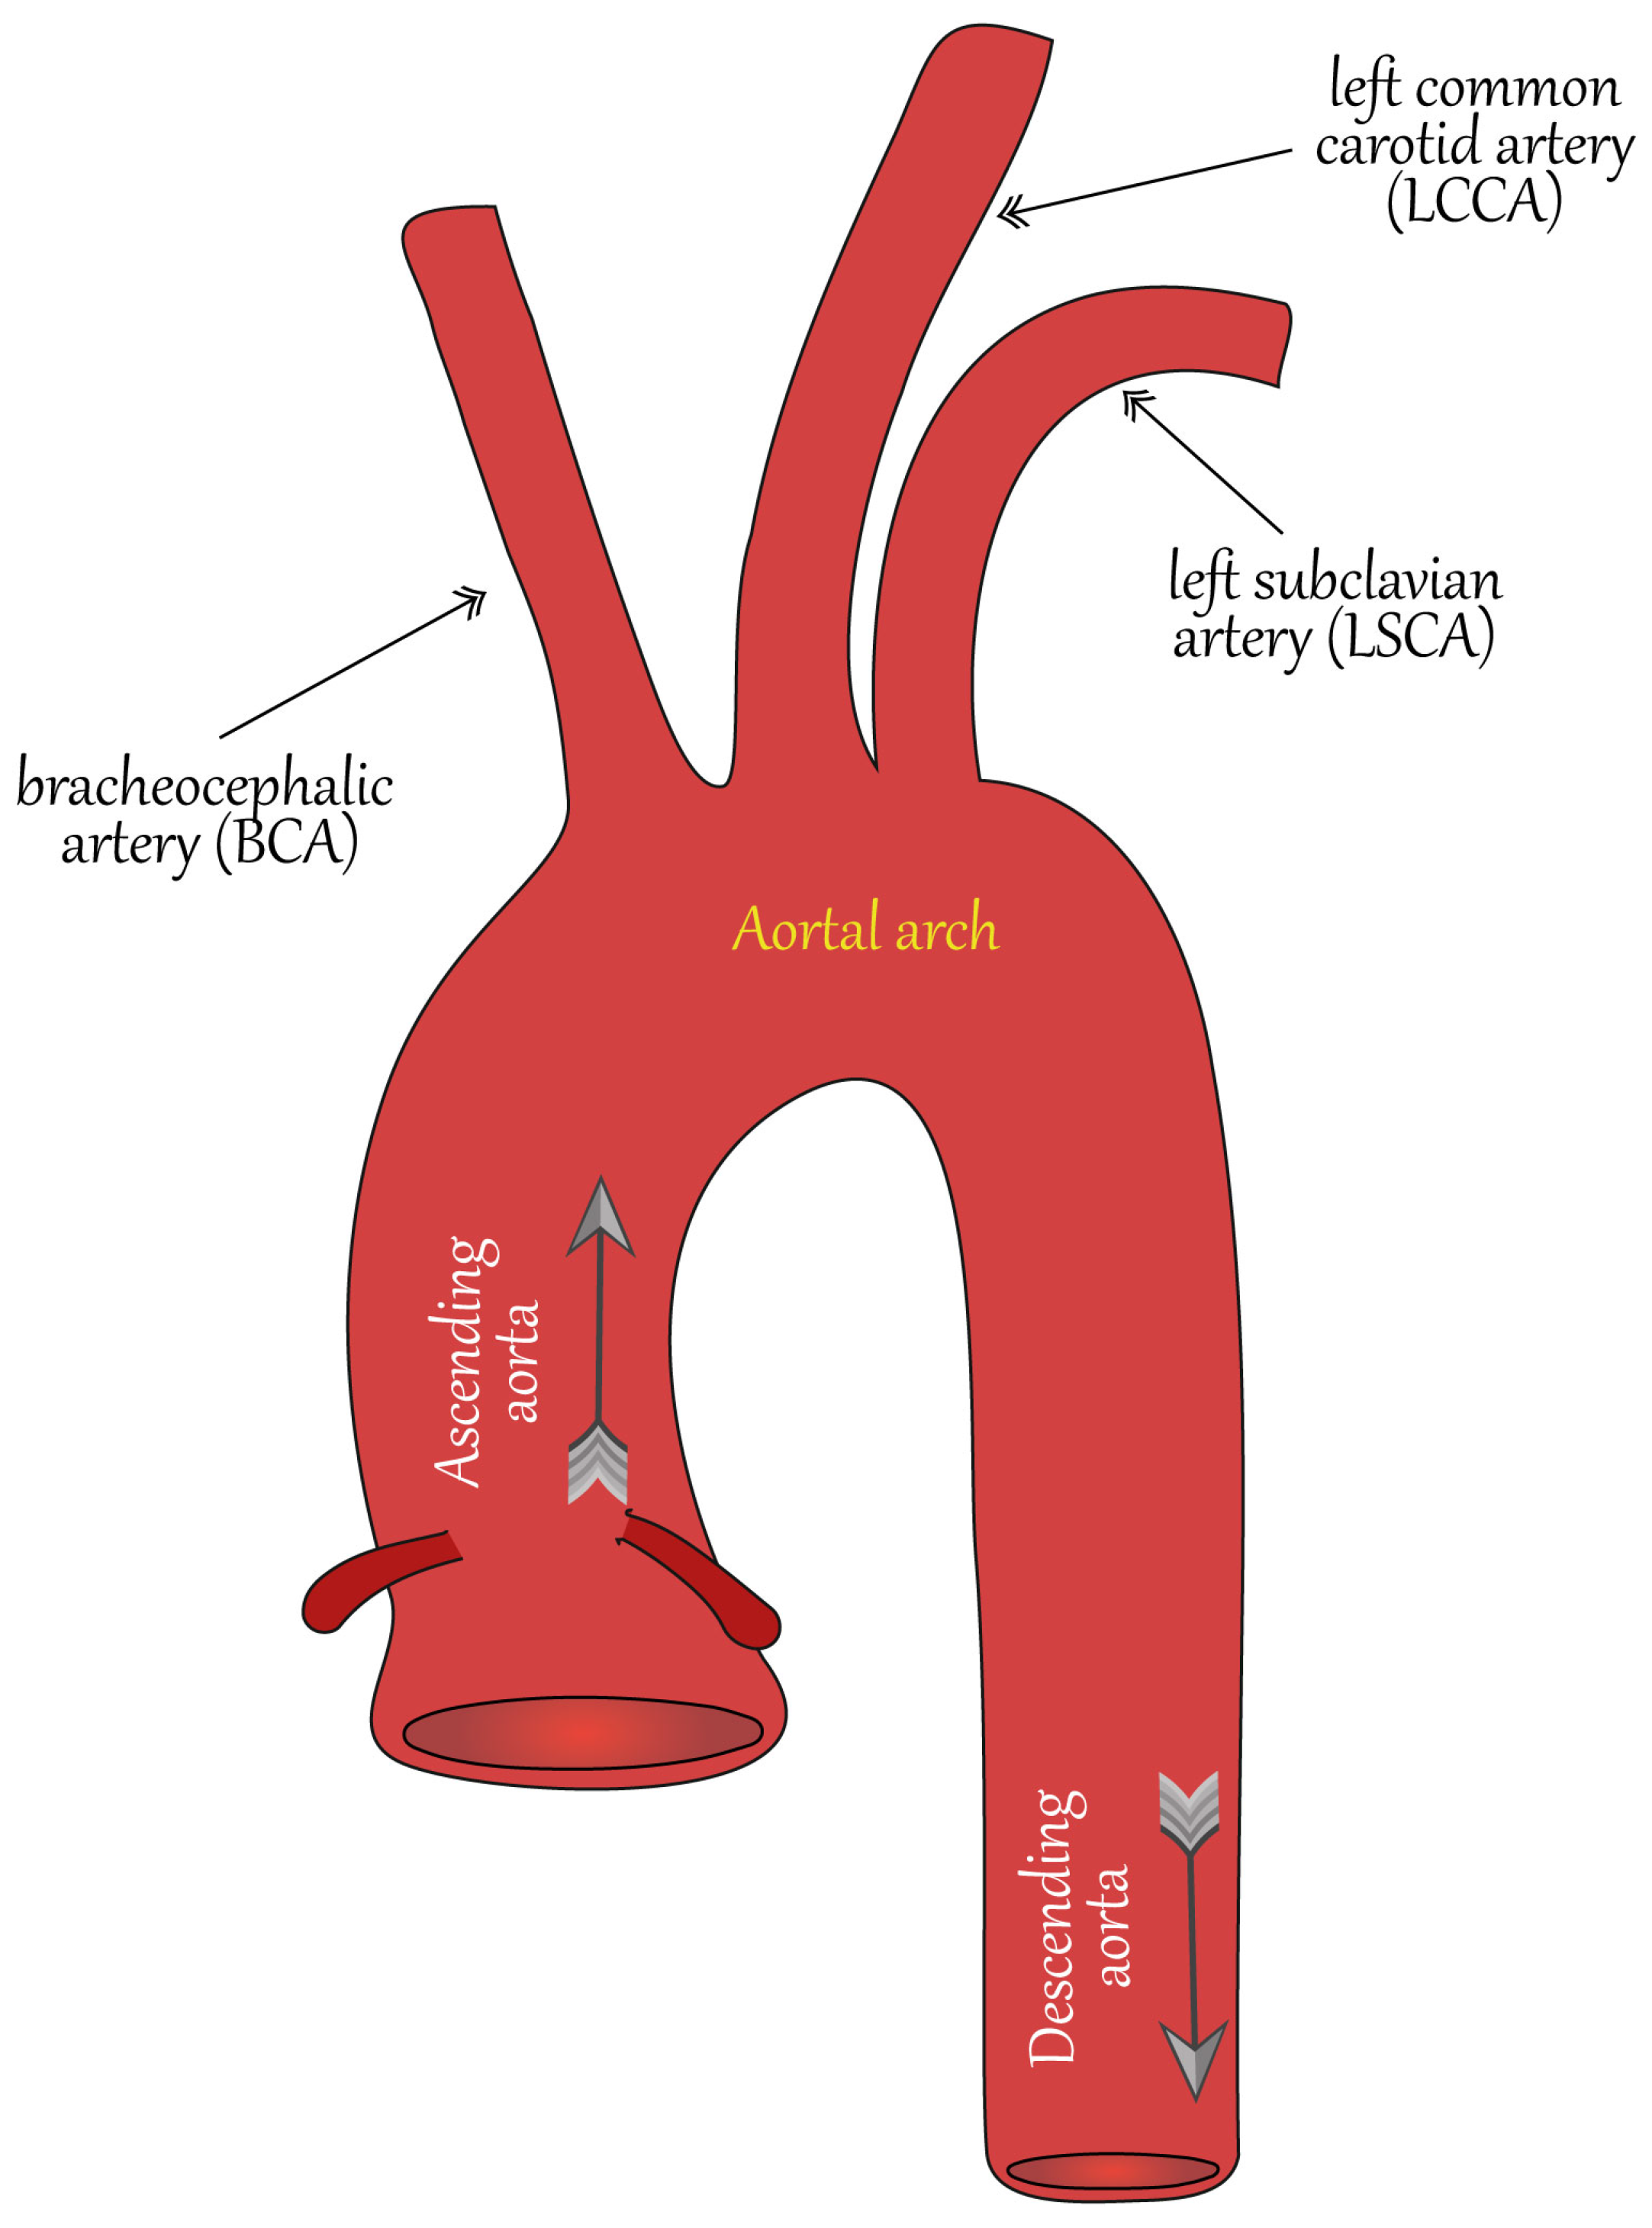

2. Vessel Surface Determination from Multi-Slice Computed Tomography Images